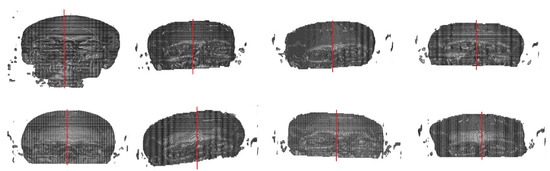

Finally, using the eight models predicted, transverse and coronal angles were calculated, and the center of the image was acquired using 3D geometric moments. Figure 11 shows the results for the deformed images.

Figure 11.

Results of the implemented method in deformed/asymmetric images.

The proposed method shows good results in obtaining the bilateral symmetric midplane of regular/symmetric images. However, for deformed images, it failed to identify the rotation for some images along with the image center. These errors are likely due to some factors: